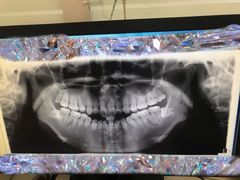

• 北京市健宫医院

• -北京市健宫医院